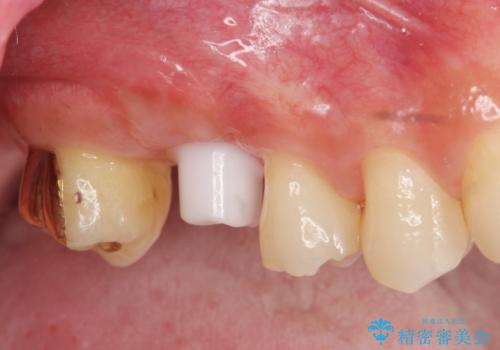

ソケットリフトを伴うインプラント補綴

治療症例の内容

- 右上の歯を喪失し機能回復を希望され来院されました。

骨量が不十分であった為、ソケットリフトを併用しインプラントによる補綴計画を立てます。